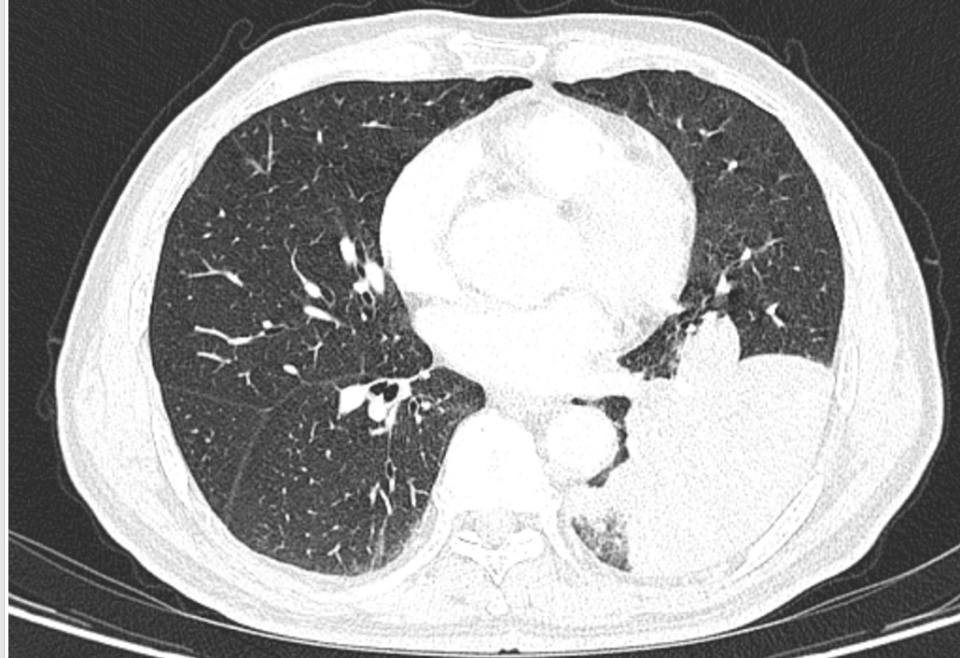

然而,从那天起,李老伯的咳嗽次数明显增多,而且还伴有浓痰,家人便带着李老伯到南京市第一医院河西院区呼吸与危重症医学科门诊就诊。胸部CT结果显示李老伯左肺下叶出现了一片“占位性病变”!

入院后,医生敏锐捕捉到一个关键细节:李老伯既往有明确的饮食后呛咳史,且此次发病前有吃鱼后呛咳的经历。因此判断,这应该不是肺部感染肿瘤,高度怀疑是气道异物,要对李老伯进行支气管镜检查!

竟意外发现在一片因炎症而充血水肿的支气管黏膜中,一个细长、坚硬的异物正死死地卡在管腔内,周围包裹着大量的脓性分泌物。

图片

原来竟然是一块长约1.6厘米的鱼骨!至此,真相大白。所谓的“肺部占位”,正是因为这块鱼骨堵塞气道,引发了堵塞性肺炎肺不张,导致李老伯长达半个月的咳嗽和咳痰。